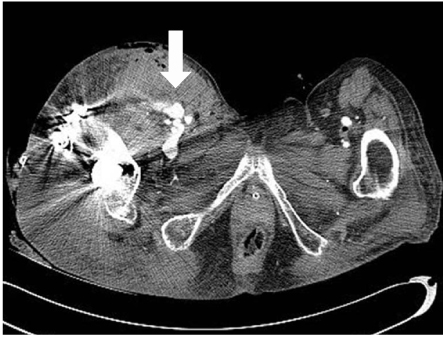

Fig. 1

(A, B) Preoperative radiographs; anteroposterior and translateral view showing subtrochanteric fracture with proximal migration of the femur shaft and deformed proximal fragment. Notice the anterior beak of the proximal fragment with severe angulation (arrow). Extensive calcifications are seen in the arteries.

An 82-year-old woman, previously in bedridden state due to general weakness, was brought to the emergency department by guardians with right hip pain and severe thigh swelling. She was hospitalized at local hospital for 2 years and during stay, only sitting position was possible. Two weeks prior to our hospital visit, she had a history of fall-down from bed but was neglected. The radiographs demonstrated a subtrochanteric hip fracture (Seinsheimer classification grade 2b) with abrupt angulation of the proximal fragment and artherosclerotic vessel (Fig. 1). Additional findings included 30~40 degrees of flexion contracture of knee with severe swelling of the injured limb, more than twice the circumference compared to the contralateral limb (Fig. 2). There were ecchymoses in the anteromedial aspect of the right proximal thigh. The femoral and pedal pulses were symmetric and palpable in both lower limbs. On admission, the blood pressure was 100/80 mmHg with the heart rate of 90 bpm. The initial hemoglobin was 9.5 g/dl with the hematocrit of 0.22. The patient was managed with Buck's traction overnight. She was taken to the operating room the next day and gently placed on the fracture table under spinal anesthesia. The proximal fragment was severely abducted, externally rotated and flexed, making the nail entry into the greater trochanter difficult. Small (3 cm) incision at greater trochanter level was made in order to insert the reduction clamp. Large amount of hematoma was evacuated right after deep fascia incision. Reduction clamp was placed through an incision to reduce the proximal fragment prior to nailing. But, soon after the reduction against the deforming force, active bleeding was observed. The bleeding point was unidentifiable due to massive bleeding and inadequate operative field. Vital sign became unstable with systolic blood pressure dropping to 50 mmHg. Massive gauze packing on the suspected bleeding site was done with rapid intramedullary nail insertion (Proximal Femur Nail, Synthes, Davos, Switzerland). Skin closure and compressive dressing was performed to stabilize the vital sign. Popliteal and pedal pulse was weak. In order to identify the injured vessel, computed tomographic angiography was performed, and active bleeding in one of the branch vessel of right deep femoral artery was suspected (Fig. 3). To further evaluate the injured vessel, emergent digital subtraction angiography was performed. At first, the left common femoral artery was punctured by using a Seldinger technique. Extravasations of contrast medium was identified on the extremity angiogram, originating from one of the minor proximal branch of right deep femoral artery, while filling a 2 cm sized pseudoaneurysm (Fig. 4A). At this stage, coil embolization was attempted to stop the ongoing bleeding. The suspected branch of right deep femoral artery was superselected by using a 2.4 Fr microcatheter (Progreat, Terumo, Tokyo, Japan). Via the microcatheter, attempts were made to completely embolize the injured artery with 13 platinum-made microcoils (Tornado®, Cook Inc., Bloominton, Minnesota, USA), including four 6/2 mm, one 5/2 mm, six 4/2 mm and two 3/2 mm microcoils. Immediately after the embolization procedure, digital subtraction angiography was performed. The angiograms demonstrated complete occlusion of the feeding vessel and the cessation of the active bleeding (Fig. 4B). No other branch except the injured terminal branch was occluded on the angiogram. The day after embolization, the packed gauze was removed surgically.

Fig. 1 (A, B) Preoperative radiographs; anteroposterior and translateral view showing subtrochanteric fracture with proximal migration of the femur shaft and deformed proximal fragment. Notice the anterior beak of the proximal fragment with severe angulation (arrow). Extensive calcifications are seen in the arteries.